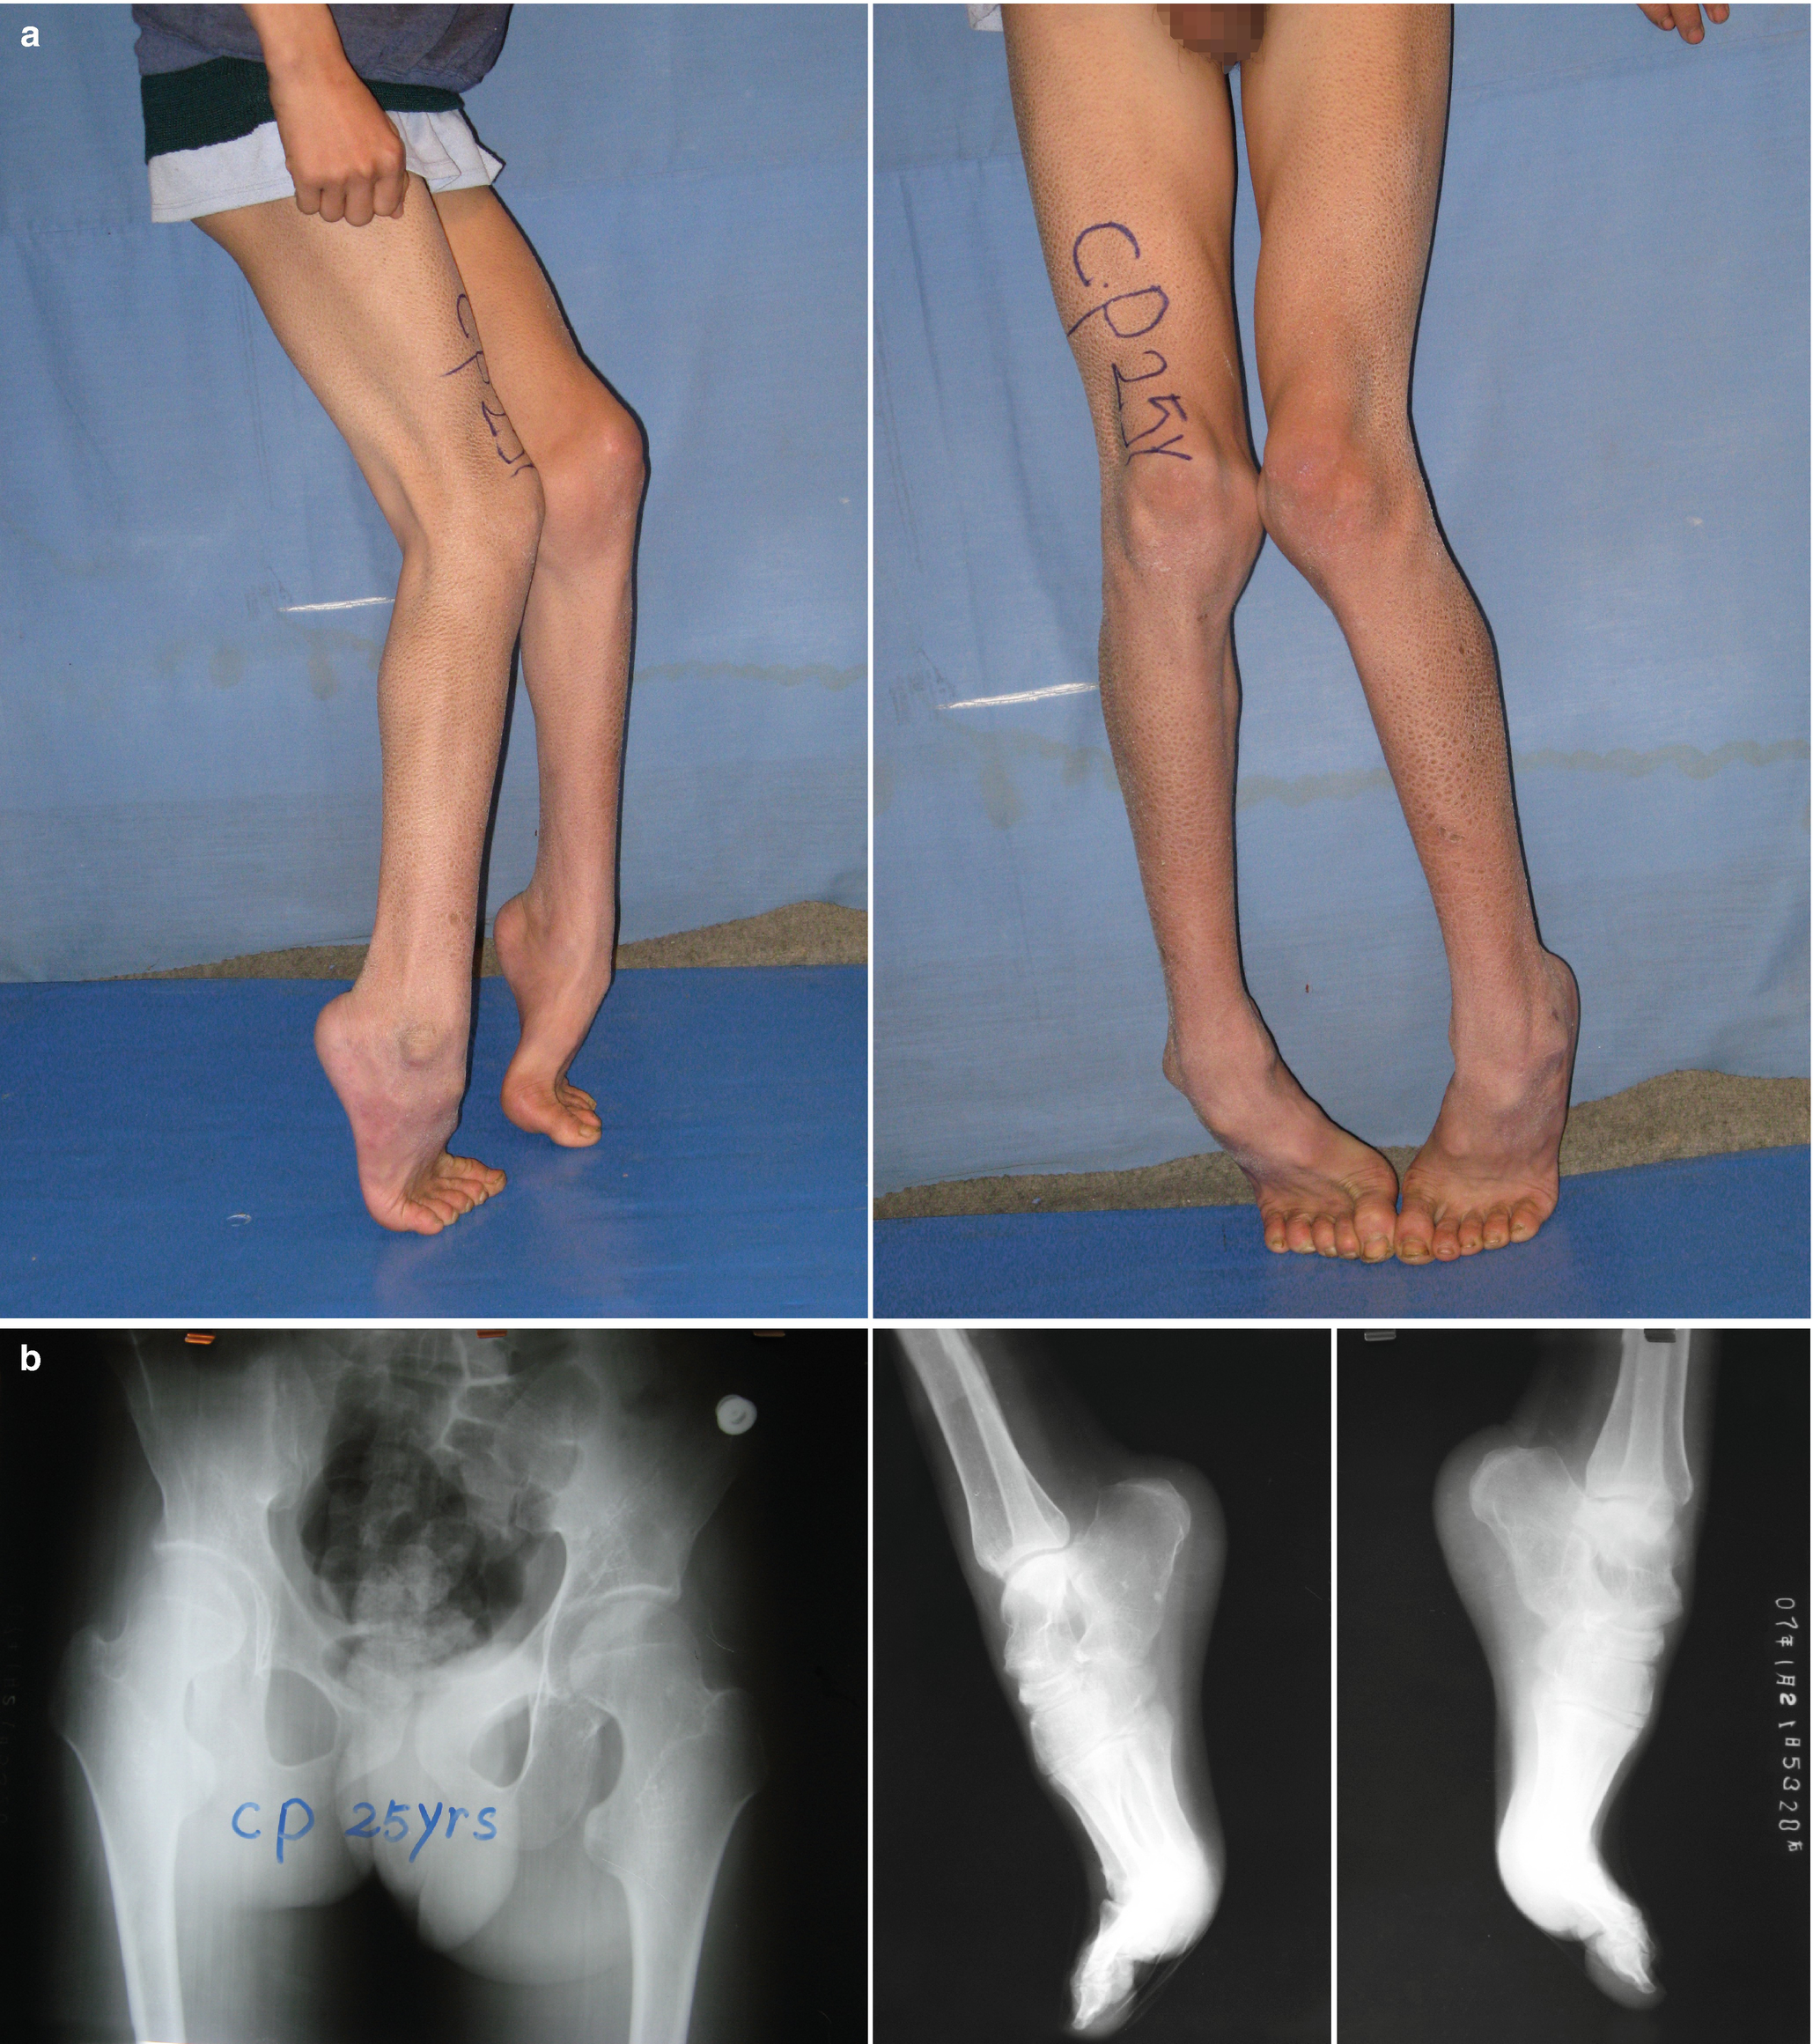

Cerebral palsy one leg longer than other. The distribution of cerebral palsy when the child is of low birth weight less than 1500 grams is as follows. A child with cerebral palsy may have one leg longer than the other to a degree that makes walking difficult or uncomfortable. Surgery can be used to shorten the longer leg but this is usually only done when the difference is more than two centimeters.

Body pain is one of the most common side effects of cerebral palsy. When one leg is longer than the other it can not only make walking more difficult but often forces you to change the way you walk to improve your momentum stability and comfort. One or both legs can be impaired different muscle groups in the body can be affected there can be difficulty walking due to stiffness or spasticity or there can be problems associated with having one limb longer or shorter than the other.